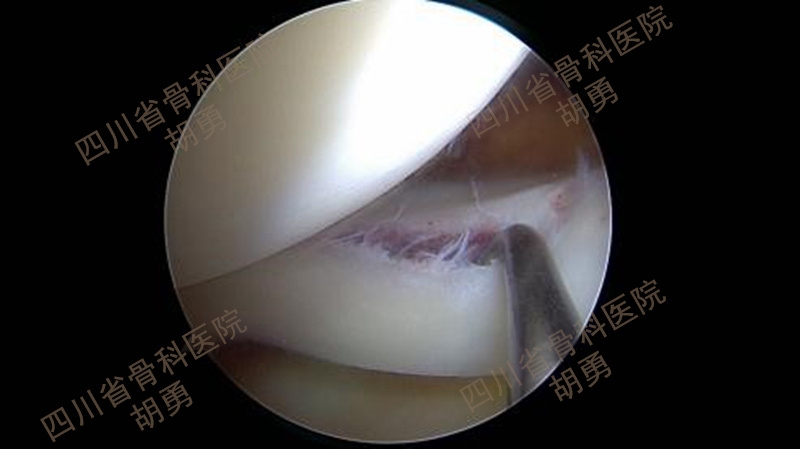

经前下外及前下内入口完成镜下检视,同期处理合并损伤。在本组病例中,常见的合并损伤主要是内、外侧半月板体部或(和)后角撕裂。对半月板后角常见的红-红或红-白区纵裂,可以通过镜下全内技术缝合挽救,如图3、4、5、6、7所示。

图3 术前MRI显示外侧半月板后角撕裂

图4 镜下证实撕裂为红—白区纵裂